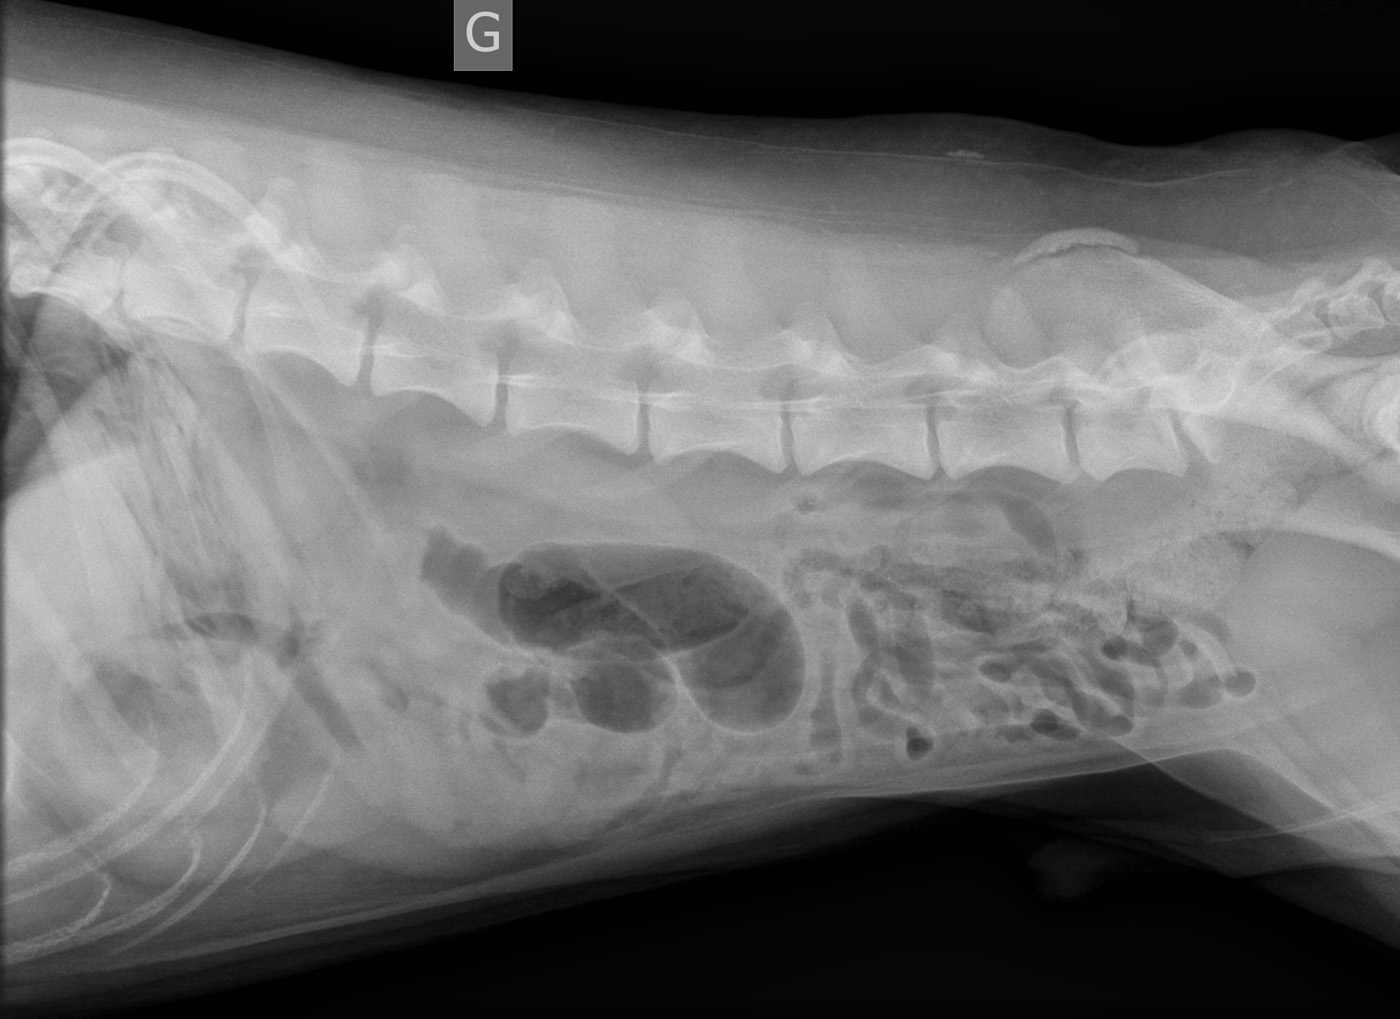

Signalement: Labrador croisé de 4 ans, mâle castré.

Histoire clinique: vomissements aigus.